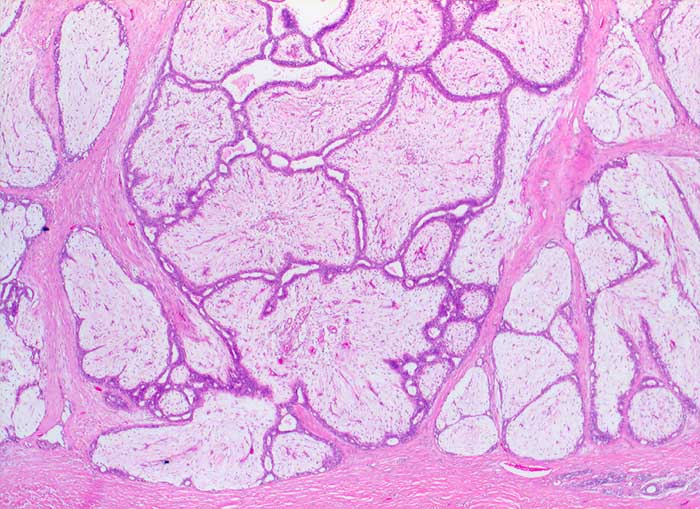

Fibroadenom

benigner Tumor

Mamma

Biphasischer scharf begrenzter lobulierter Tumor bestehend aus verzweigten epithelial ausgekleideten Gangstrukturen, die von einem zellarmen ödematösen Stroma komprimiert werden.

Histologische Diagnose: Fibroadenom mit ausgeprägtem Stromaödem

Zytologische Diagnose: Fibroadenom / phylloider Tumor